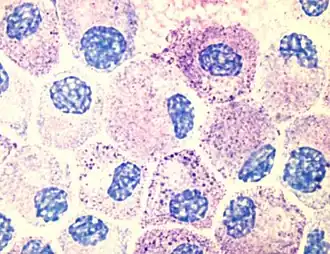

Морфологически тучные клетки очень близки к базофилам в кровотоке. И тучные клетки, и базофилы содержат базофильные гранулы с гепарином и гистамином. Однако между двумя типами клеток есть и различия в строении: так, у тучных клеток ядро округлое, а у базофилов разделено на доли. Округлое ядро мастоцитов находится центрально, часто замаскировано цитоплазматическими гранулами[5]. Тучные клетки и базофилы связываются с Fc-участками молекул иммуноглобулинов E (IgE), связавшими антиген (кросс-связывание), в результате чего запускается высвобождение содержимого гранул. Из-за сходства с базофилами тучные клетки иногда называют тканевыми базофилами. Кроме того, базофилы и тучные клетки происходят от одного и того же костномозгового предшественника, экспрессирующего CD34. Базофилы покидают костный мозг зрелыми, в то время как созревание тучных клеток завершается после их оседания в тканях. Место оседания тучных клеток может влиять на некоторые их свойства[6].

Тучные клетки присутствуют в большинстве тканей и, как правило, располагаются вблизи сосудов и нервов. Они особенно многочисленны в тканях, залегающих на границе организма с внешней или внутренней средой: коже, слизистой лёгких и пищеварительного тракта, а также в ротовой и носовой полостях и конъюнктиве[6]. В подслизистом слое слизистых, дерме, серозных оболочках, селезёнке и периваскулярной соединительной ткани тучные клетки содержатся в количестве 104—106 на 1 г ткани. На гистологических препаратах тучные клетки легко визуализируются при помощи окрашивания толуидиновым синим или алциановым синим[7]. Для тучных клеток характерен эффект метахромазии при окрашивании анилиновыми красителями из-за большого количества кислых радикалов протеогликанов[5].

Тучные клетки достигают 10—20 мкм в диаметре и имеют овальную форму с ворсинчатой поверхностью. Композиция молекулярных маркеров на поверхности тучных клеток выглядит как FcεRI+CD13+CD29+CD45+CD117+СD123+. FcεRI являются высокоаффинными рецепторами IgE. CD117 представляет собой рецептор для фактора стволовых клеток (SCF), а CD123 — рецептор для IL-3. Именно SCF и IL-3 являются основными факторами роста для зрелых тучных клеток. Также тучные клетки несут на своей поверхности рецепторы для компонентов комплемента C3b и C3d, что свидетельствует об их участии в реакциях врождённого иммунитета. Кроме того, тучные клетки несут MHC обоих классов, и благодаря наличию MHC класса II и CD86 тучные клетки функционируют как антигенпрезентирующие клетки, особенно в отношении Th2-клеток[8].